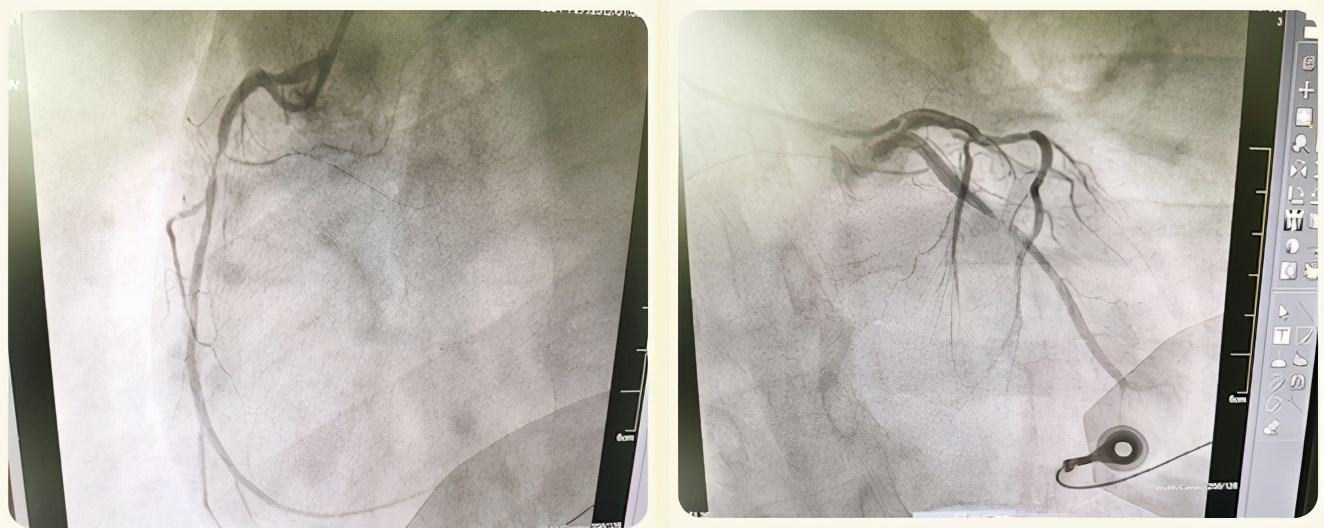

李春海主任完成左桡动脉穿刺,李文军医生也同步完成右股静脉穿刺。冠脉造影显示患者冠脉主要的三支血管皆存在重度狭窄,其中供血面积极大的回旋支次全闭塞并可见血栓影,此病例在我们工作中多见,但在如此年轻的患者中罕见。

患者血管情况很严重,病情也极不稳定,此刻出现了心率减慢,血压降低......陈志熠护士给予升压药及提升心率药物,密切观察患者生命体征;胥玉菊护士给介入医生准备手术材料。李春海主任专注娴熟地送入一根细细的导丝,进行球囊扩张;李文军医生熟练的配合手术操作......大家小心翼翼又有条不紊地展开救护手术工作,这其中的每一步操作都直接决定着患者的预后。

手术结果非常圆满,患者的堵塞“罪犯"血管得以重建,患者病情逐渐地平稳下。“医生,我胸不疼了,谢谢”,患者饱含感激微弱的一句话,让大家悬着的心都落了下来,被一份慰籍填满。患者从送入医院大门到开通冠脉血流仅仅过去多70分钟,而从胸痛到手术毕也才仅仅过去2个小时。